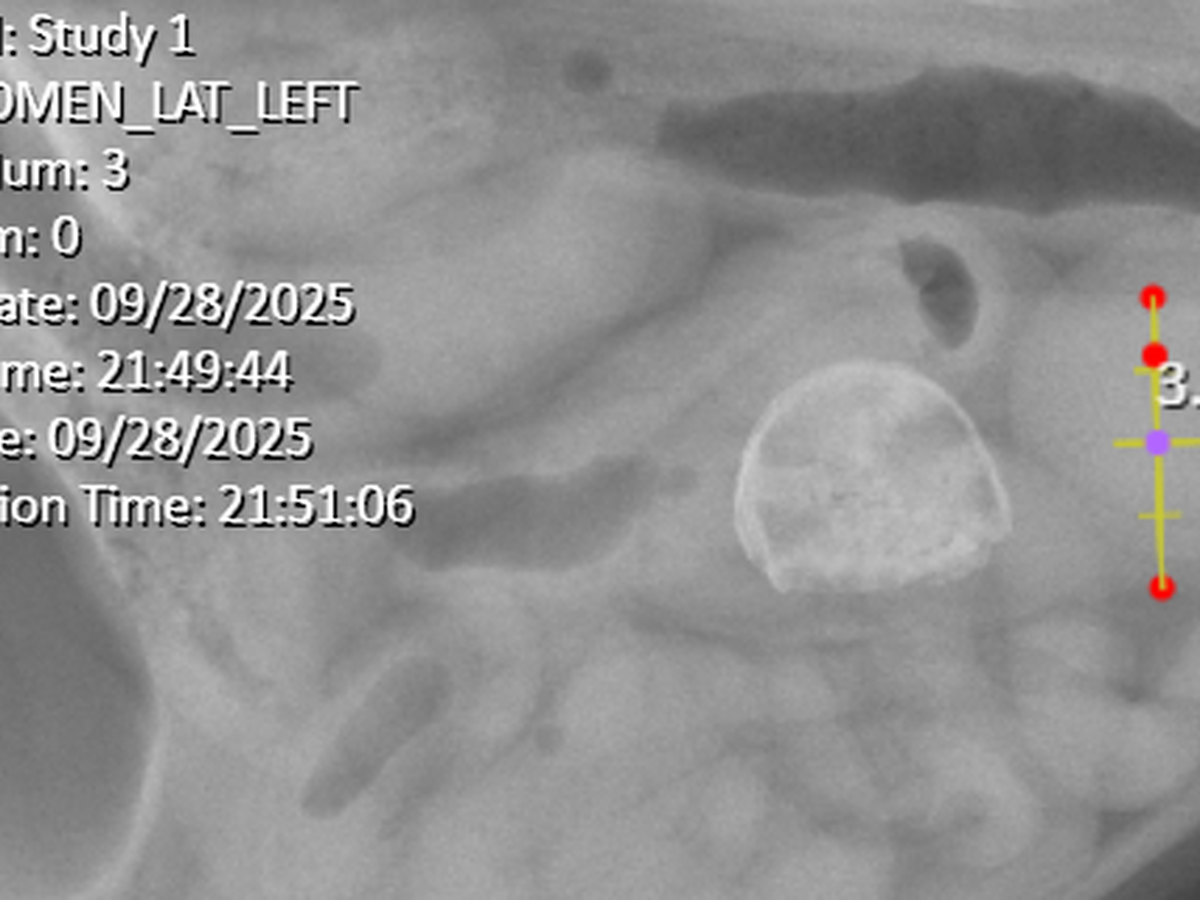

Hi! I'm Jude, I'm 24 years old. This is Parker, and as of this month he's 7 years old! I brought him home as a gift for my eighteenth birthday back in 2018, when he was just a couple months old. Parker is incredibly friendly and loving, a little guy that demands attention and cuddles at every opportunity. Recently, he's been getting sick. It's been pretty bad. We'd tried supervised feeding, changing his food, and nothing would work. He's been lethargic and showing clear signs of being in pain. Tonight (9/28/25) we took him to the vet because he refused his dinner-- something he's never done before. After a couple hours of tests and xrays, they found a foreign object in his stomach as well as some distension. Neither we nor the vets can tell what exactly it is, but we have been informed that he will more than likely need surgery to have it removed. We've been quoted somewhere between $3k-$5k. Please. I know it's cliche for people to say but he's my baby. I'm not ready to lose him. My partner and I are both college students and can't afford to do this on our own. I'm sorry. I know it's a lot and I am so sorry. But please, I can't lose my boy. Anything helps at all.